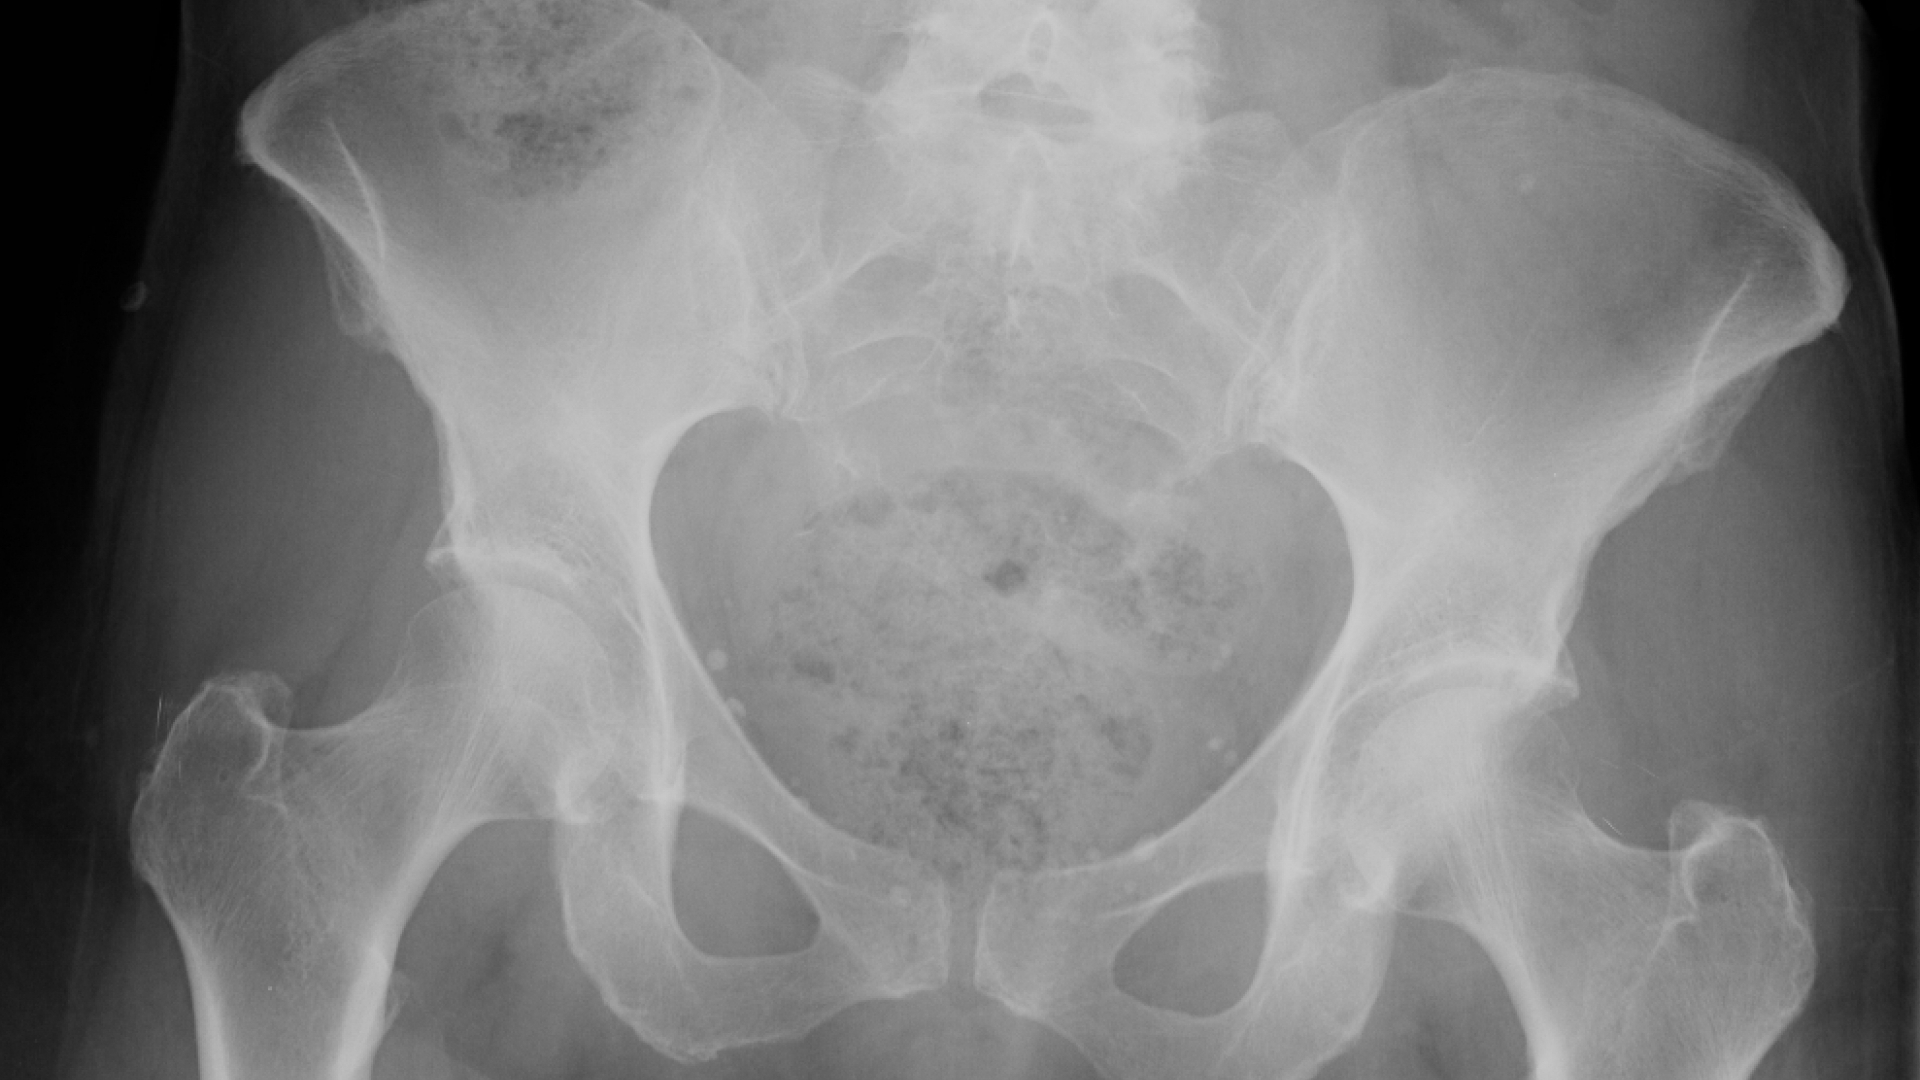

這種罕見的腫瘤主要沿軸向骨骼表現,常影響骶尾部 (約 50%)、顱底 (約 35%),以及活動脊椎 (約 15%),如頸椎或腰椎。雖然 脊索瘤(脊索骨腫瘤) 本病呈現緩慢的生長,但具有侵襲性且容易復發,因此早期發現和先進的治療策略至關重要。

脊索瘤通常根據腫瘤大小、位置、侵襲程度和是否有轉移痕跡進行分期。一般的分期使用 MRI 和 CT 成像來概括疾病的範圍:

• 本地化: 腫瘤仍控制在原來的組織中,沒有遠端擴散。

• 本地先進: 廣泛的區域組織侵襲,但無遠端轉移。

• 轉移性: 腫瘤遠端擴散的罕見病例,常見於肺部和骨骼。